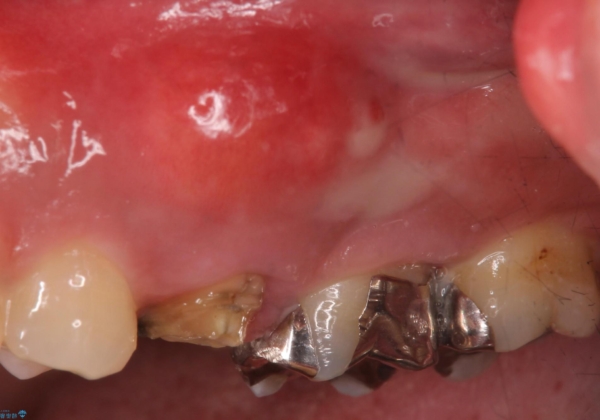

歯茎が腫れる インプラントでの治療

- 40代女性

- 10ヶ月

- 5-10回

- 左上5/インプラント:242,000円 骨増生:55,000円 カスタムアバットメント:110,000円 インプラント用仮歯:22,000円 ジルコニアクラウン:121,000円 合計550,000円費用は治療当時の料金となります